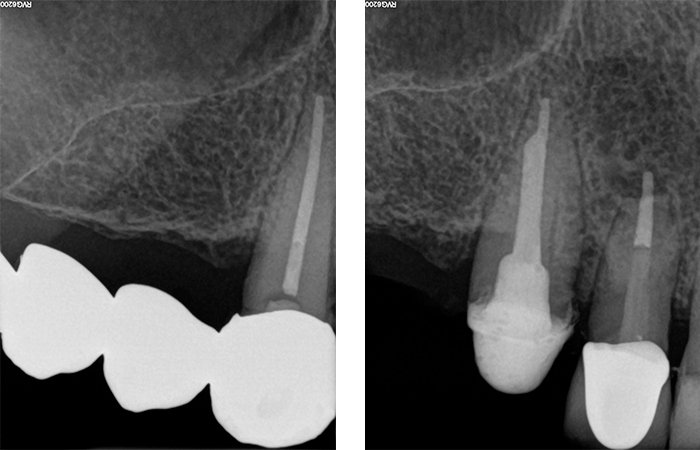

La paziente, di 68 anni, buona salute generale, presentava un grave problema al ponte 17-15-14 con dolore alla masticazione, mobilità e grave perdita ossea su 17 e 12 (Figs. 1, 2, 3).

Radiografie iniziali 13, 12

Fig. 2, 3 - Radiografie iniziali 17, 13, 12 con estrazione del 17 e guarigione in zona Tuber dopo 3 mesi

Figs. 32, 33, 34 - Radiografie finali impianti 17, 15, 14 ad un anno dal carico con guarigione del rialzo di seno trans-crestale del 15, impianto pterigoideo 17 e Socket Shield 12